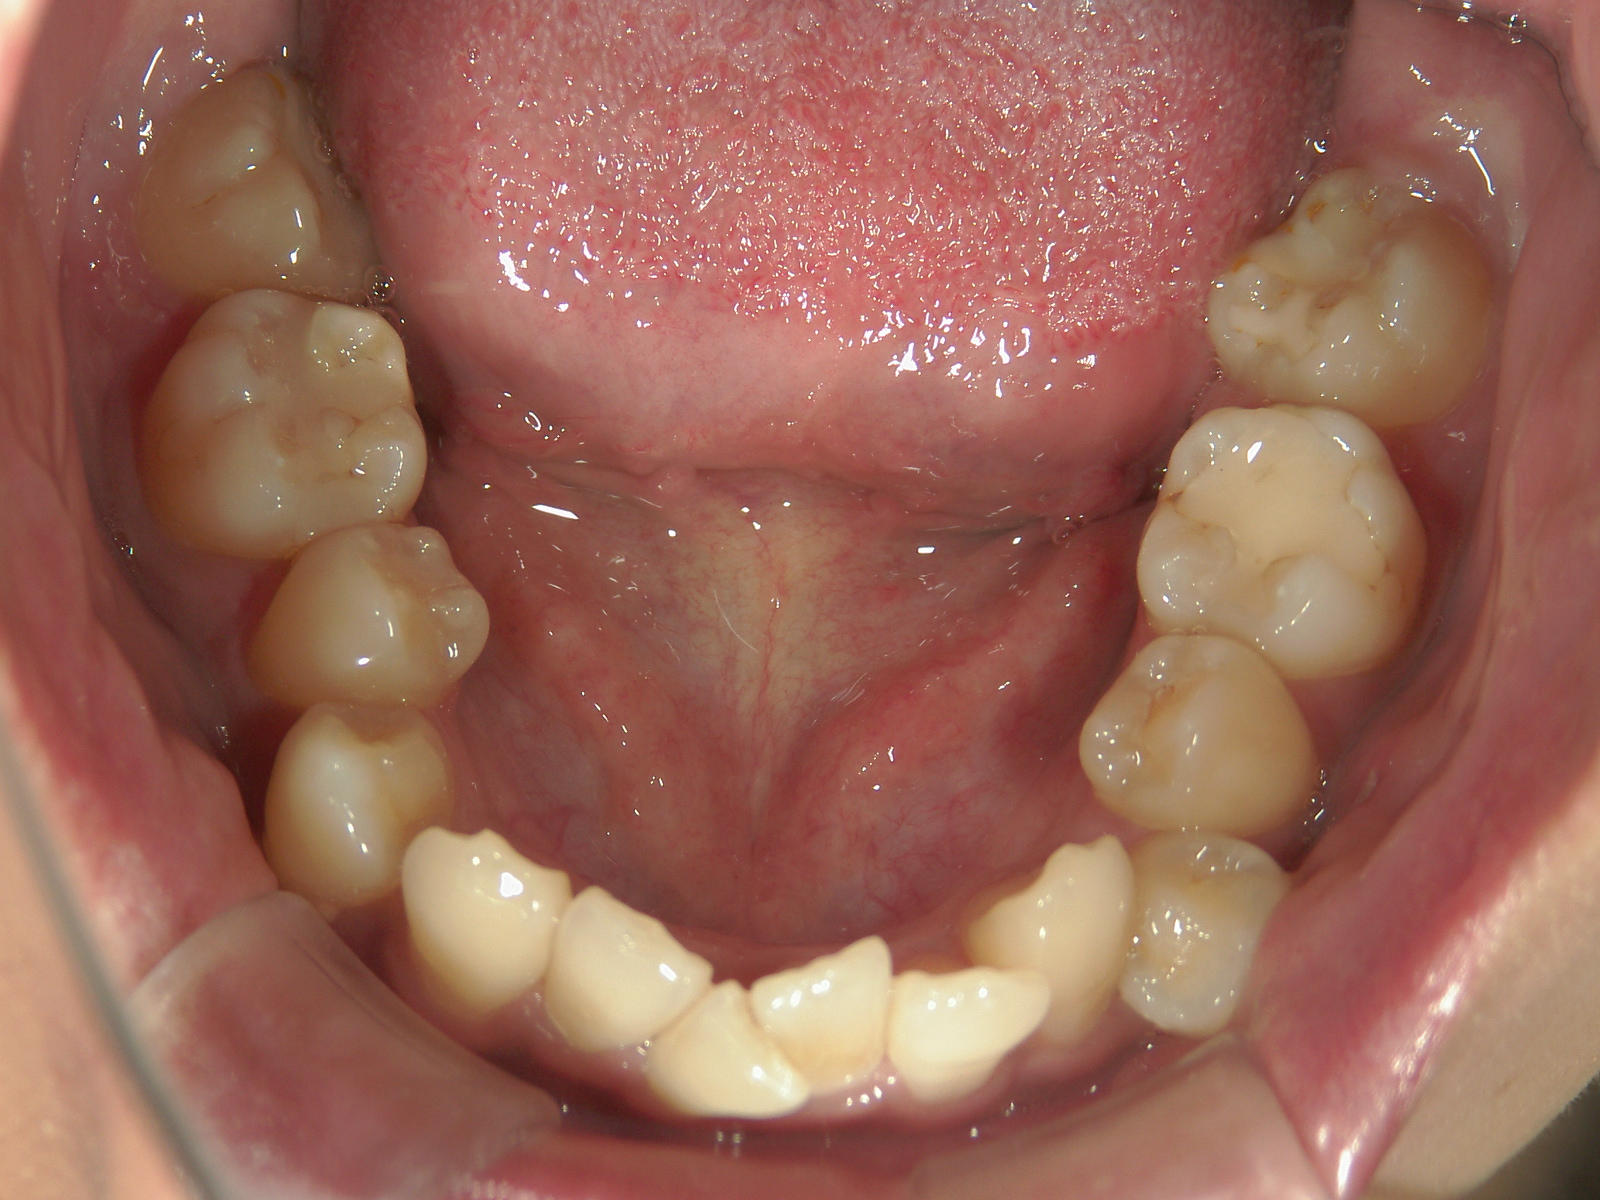

全顎ワイヤー矯正 症例(6)

主訴: 噛み合わせが悪い

①叢生を改善しました。

カテゴリー : ガタガタ(叢生) , 噛み合わせが深い(過蓋咬合)